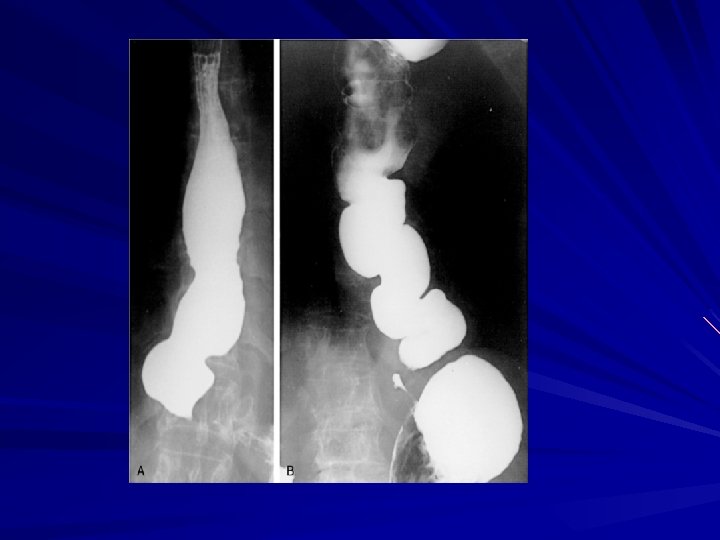

GASTROESOPHAGEAL REFLUX DISEASE LES has the primary role of preventing reflux of the gastric contents into the esophagus GERD may occur when the pressure of the high-pressure zone in the distal esophagus is too low to prevent gastric contents from entering the esophagus

GASTROESOPHAGEAL REFLUX DISEASE GERD is often associated with a hiatal hernia the most common is the type I hernia, also called a sliding hiatal hernia Type II and III hiatal hernias are often referred to as paraesophageal hernias and they may be associated with GERD Type IV when there is other organ herniated into the chest (Spleen , Colon)

Diffuse Esophageal Spasm DES is a hypermotility disorder of the esophagus is seen most often in women and is often found in patients with multiple complaints The basic pathology is related to a motor abnormality of the esophageal body that is most notable in the lower two thirds of the esophagus

Diffuse Esophageal Spasm the esophageal contractions are repetitive, simultaneous, and of high amplitude

Symptoms and Diagnosis irritable bowel syndrome and pyloric spasm, may accompany DES, whereas other gastrointestinal problems, such as gallstones, peptic ulcer disease, and pancreatitis, all trigger DES The diagnosis of DES is made by an esophagram and manometric studies